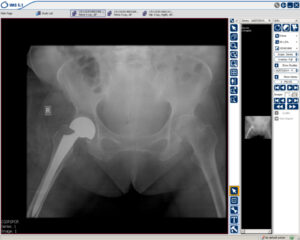

Mobilitas Cepat: Penggantian Pinggul Memungkinkan Penyanggaan Beban Segera untuk Wanita Berusia 70 Tahun

Contoh dari seorang wanita berusia 70 tahun yang patah tulang pinggul dan menjalani penggantian pinggul sehingga segera mampu berdiri lagi.